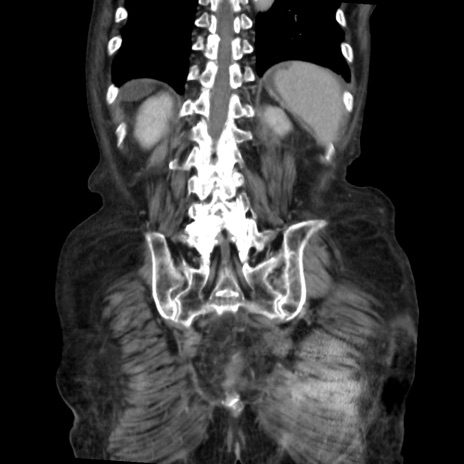

矢状断像

【症例】80歳代 女性

【主訴】腹部膨満感

【現病歴】他院にて肝硬変にてフォロー中。1週間前から便秘、腹部膨満感、臍部腫瘤あり受診となる。

【既往歴】肝硬変

【身体所見】腹部膨隆あり、皮膚変化なし、疼痛なし。

【データ】WBC 4600、CRP 0.25